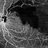

- OCTA, branch retinal vein occlusion (BRVO), ST BRVO, CNP areas

- OCT-Angio image of the LE of a 76 year old hypertensive male with history of old superotemporal branch retinal vein occlusion status post 3 anti VEGF injections received in 2012.Vision was 6/9 in left eye. OCTA shows a large CNP area .